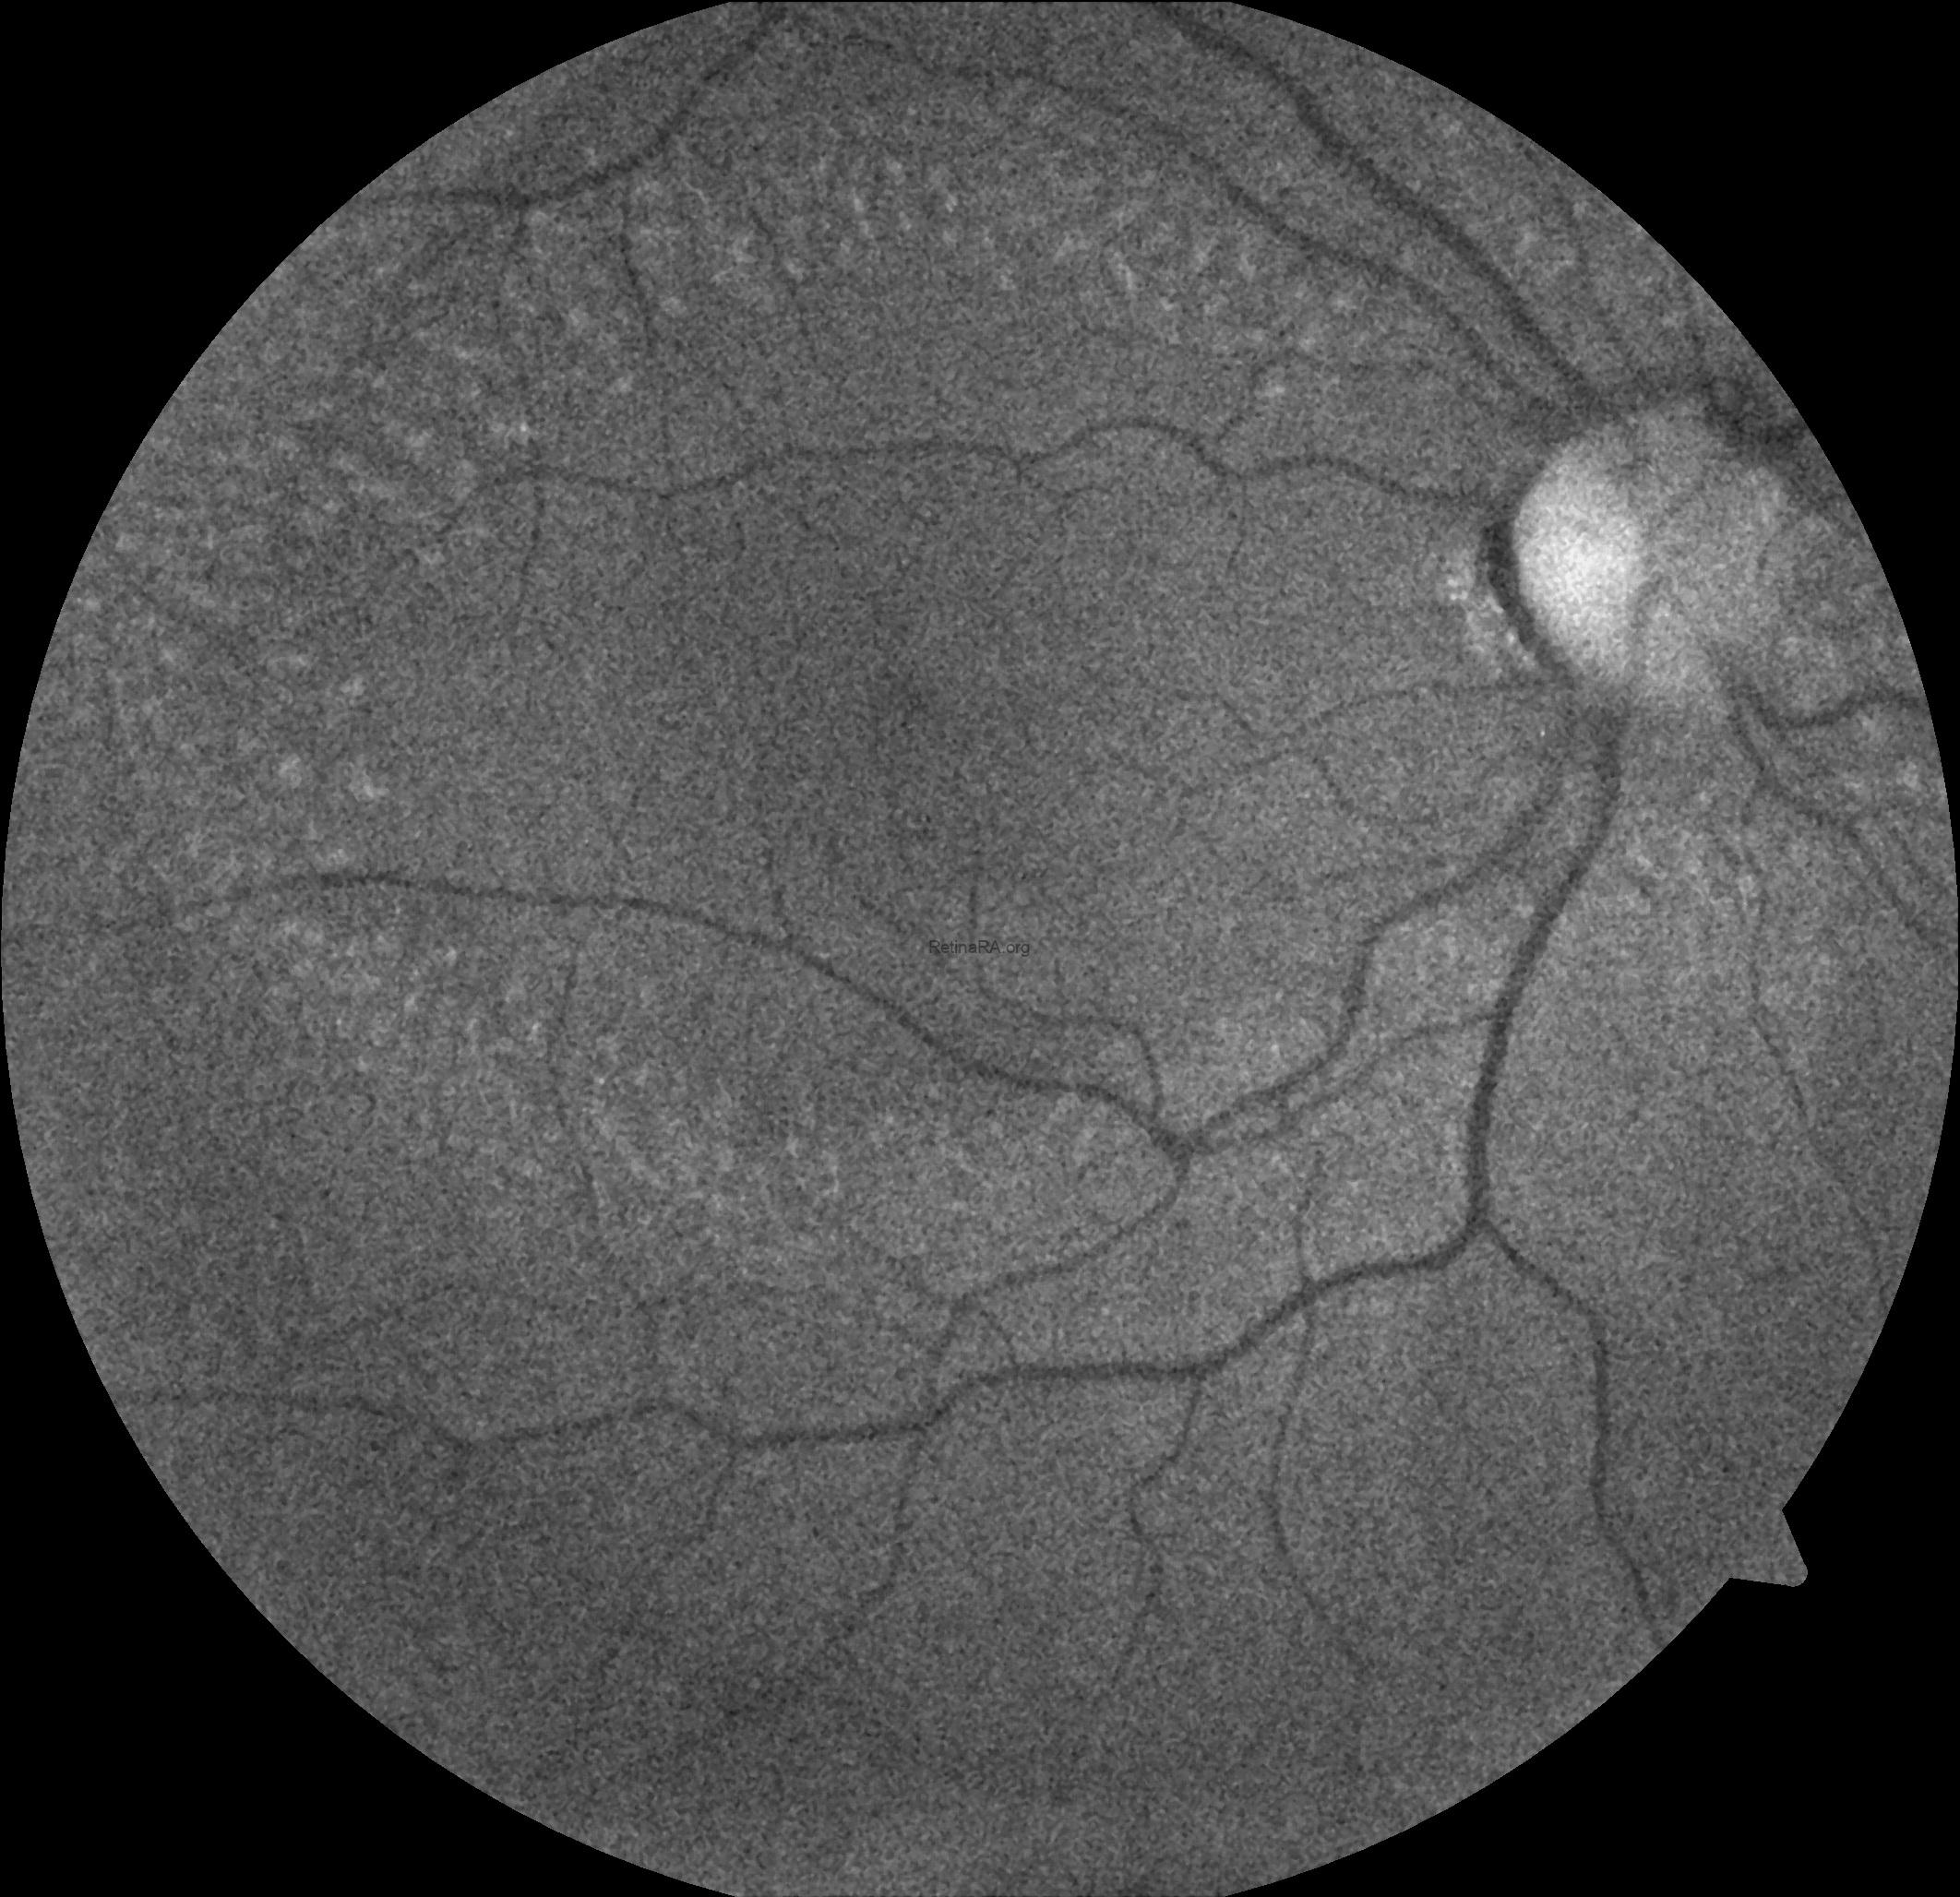

Ophthalmoscopic examination reveals scattered, discrete yellowish-white dots at the level of the retinal pigment epithelium, predominantly outside the macula. While these lesions are generally stable over time, partial regression has been documented in long-term follow-up. Histopathologically and functionally, these deposits are thought to represent accumulated retinoid intermediates, extending from the RPE–Bruch membrane complex into the outer retinal layers, including the outer nuclear layer.

Optical coherence tomography (OCT) provides valuable structural information in fundus albipunctatus. OCT imaging typically demonstrates focal hyperreflective material originating from the RPE and projecting into the outer retinal layers, correlating with the punctate lesions seen on fundus examination. On fundus autofluorescence imaging, a diffusely reduced background autofluorescence is commonly observed, reflecting impaired retinoid metabolism and RPE dysfunction related to disruption of the visual cycle.